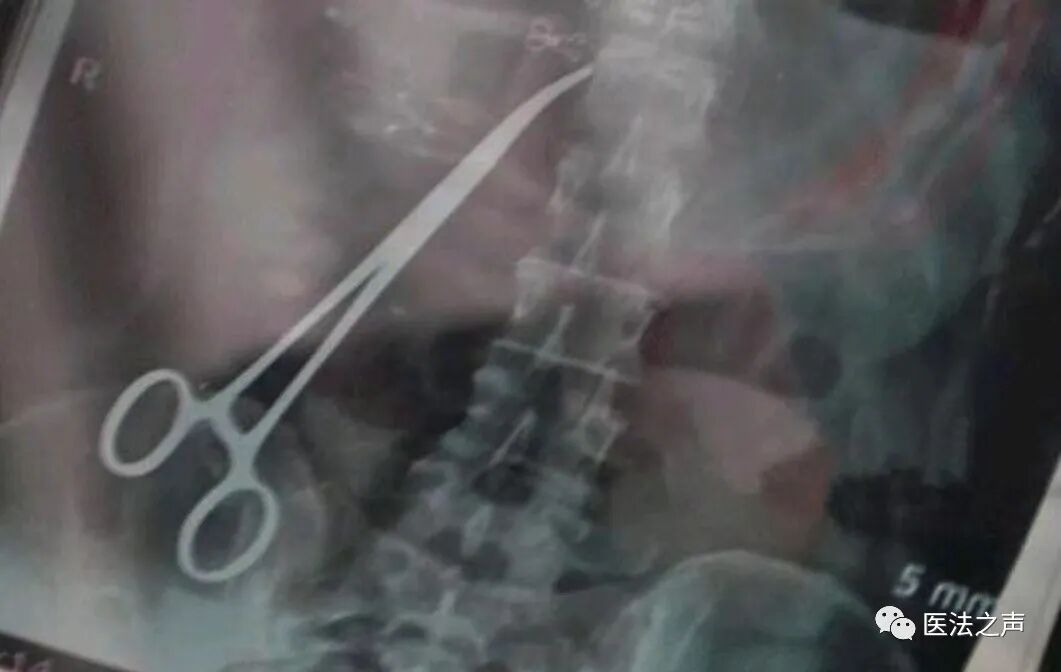

就在一个月前,祝女士怀有的三胎进行了流产,原因是因为检查中孩子不发育,就在做完流产以后,7月31日发现腰疼的特别的厉害,随后到乡医院拍了一个片子,发现腹中竟然有一把止血钳。。

当地卫健委介入以后,确定了这是一场重大的医疗事故,如果调查清楚后将进行严肃处理。卫健委希望祝女士通过手术将腹中的止血钳取出,因为害怕取出后没有了证据,医院会进行一些推辞,所以迟迟不打算将止血钳取出。

9月3号,祝女士到达郑州人民医院并再次确定了止血钳的存在和位置,然后进行手术前的各种准备,卫健委也会在取钳手术中全程在现场,保证鉴定公正、客观。